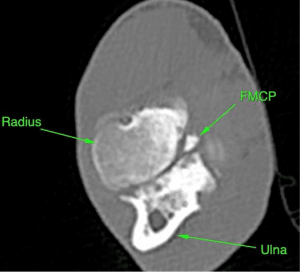

The elbow is the joint formed by the humerus, radius and ulna. Dysplasia results when the bones do not match each other well (known as incongruency). There are various abnormalities but the result of these is overloading at parts of the joint. The most common problem is fragmentation of the medial coronoid process. This lip of bone on the ulna can become detached resulting in a fragment of bone and cartilage, leading to pain in the joint.

Conditions like fragmented coronoid process usually require CT imaging for accurate diagnosis. CT uses X-rays like traditional radiographs but can provide much more detail and allow a 3D image to be constructed. The detail is required because the area may be small (sometimes only a crack running across the area). We can also assess the incongruency (how well the joint fits together) to some extent.